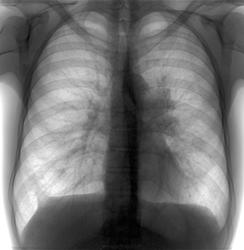

Снижение прозрачности левого легкого, тени в проекции корня. Доп. тень в проекции подмышечных узлов.

а это мне кажется или что-то есть в правой лопатке?

Да - есть, очевидно остеохондрома, но это требует уточнения.

Поддержу мысль о саркоидозе лимфатических узлов. Плевро-диафрагмальная спайка справа. Значит, процесс был воспалительный. Почему нет бокового снимка?

При саркоидозе обычно корни выглядят более менее симметрично, а здесь наоборот. Может и канцер выскочить. Провести ТМГ или КТ.

классических признаков пневмонии, предполагаю инфильтративный туберкулез 6 сегмента левого легкого. Ждем боковой, если имеется.

Пневмония С6, нужно бы посмотреть динамику после лечения.